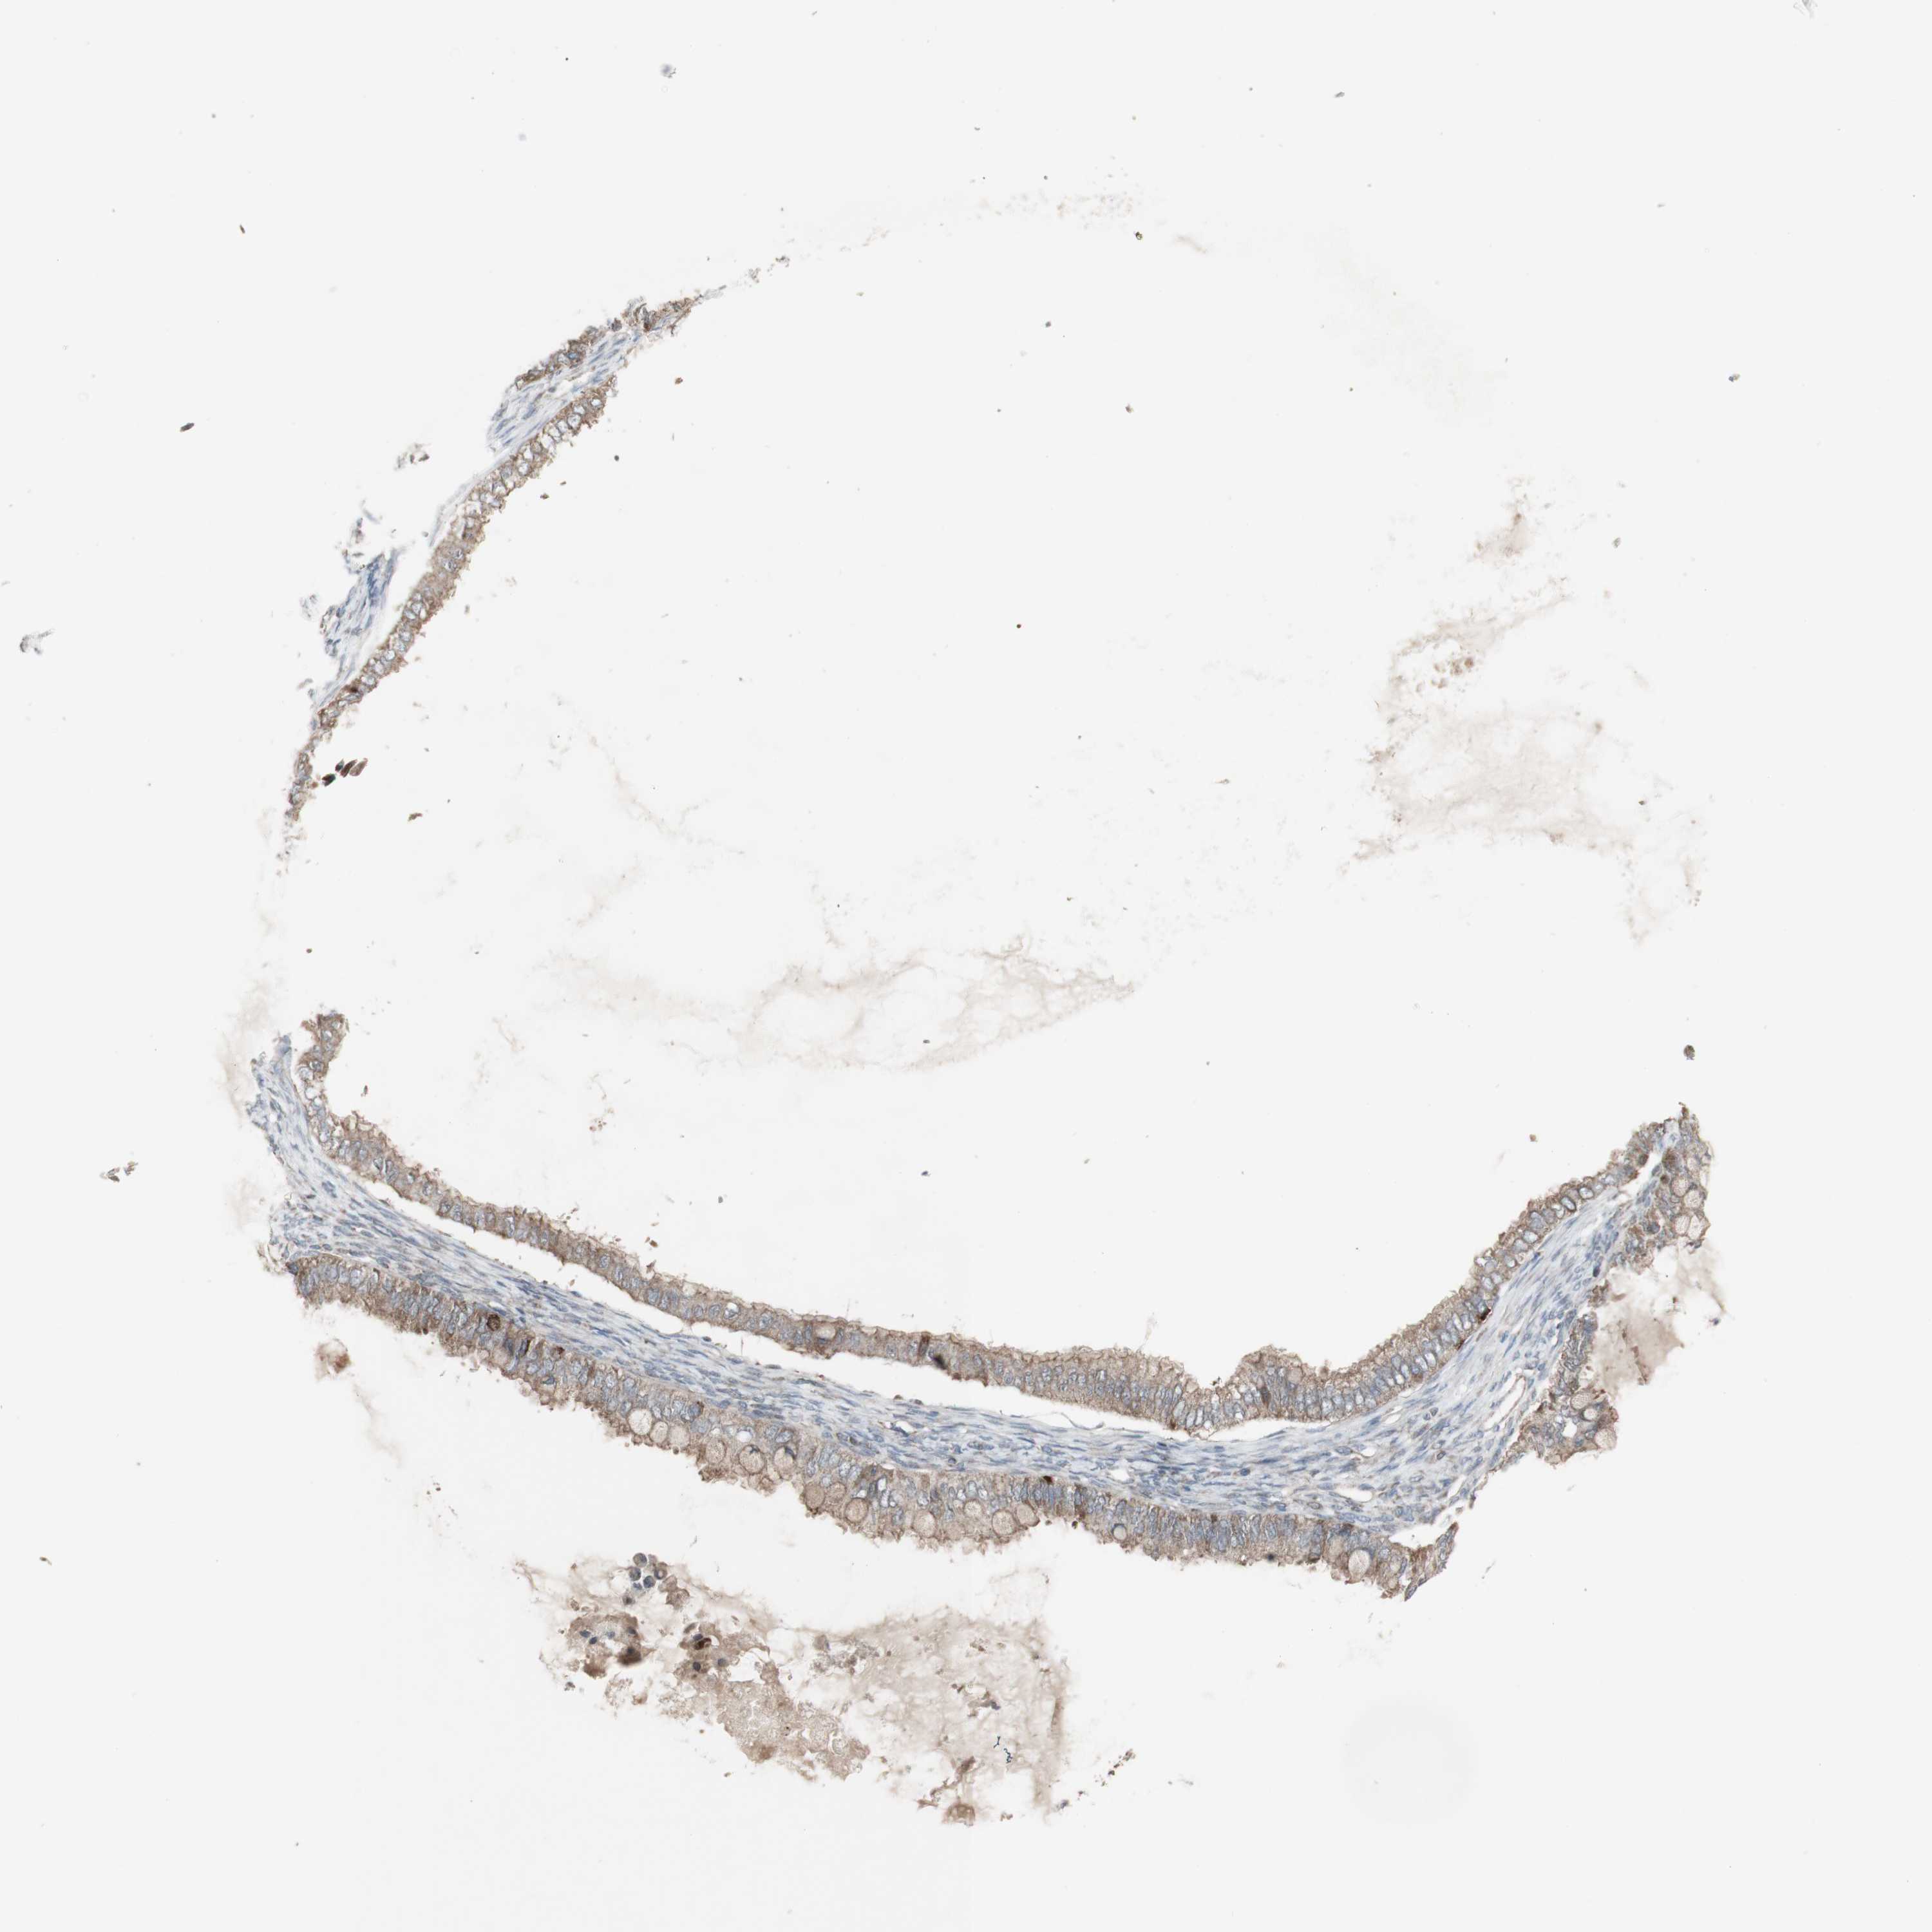

OVARIAN CANCER - Protein expressioni

A mouse-over function shows sample information and annotation data. Click on an image to view it in a full screen mode. Samples can be filtered based on level of antibody staining by selecting one or several of the following categories: high, medium, low and not detected. The assay and annotation is described here.

Note that samples used for immunohistochemistry by the Human Protein Atlas do not correspond to samples in the TCGA dataset.

Antibody stainingi

Antibody staining in the annotated cell types in the current human tissue is reported as not detected, low, medium, or high, based on conventional immunohistochemistry profiling in selected tissues. This score is based on the combination of the staining intensity and fraction of stained cells.

Each image is clickable and will lead to virtual microscopy that enables deeper exploration of all samples and also displays staining intensity scores, fraction scores and subcellular localization as well as patient and tissue information for each sample.

Antibody CAB005374

Cystadenocarcinoma, mucinous, NOS